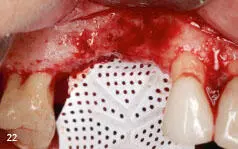

Figs 219 to 221 Vertical augmentation of the anterior maxilla - фото 76 Figs 219 to 221 Vertical augmentation of the anterior maxilla cont - фото 77 Figs 219 to 221 Vertical augmentation of the anterior maxilla cont - фото 78

Figs 2-19 to 2-21 Vertical augmentation of the anterior maxilla (cont).